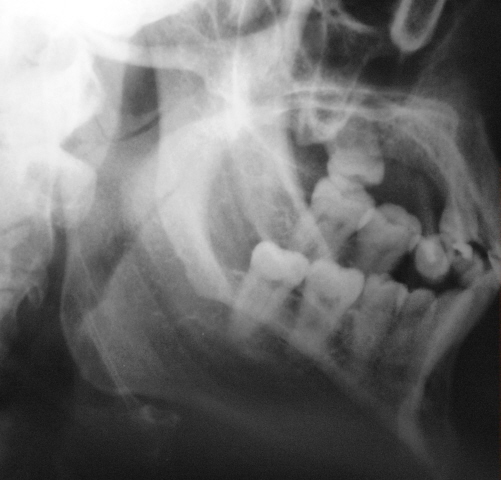

А это визави.

А у нас так ломают челюсти

на мой взгляд здесь перелом суставного отростка